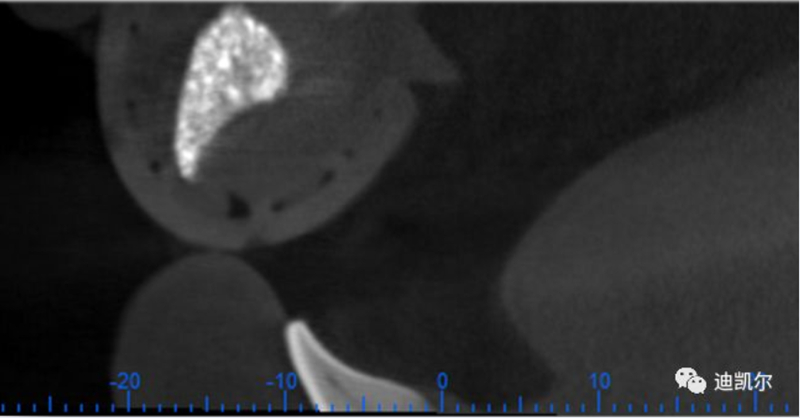

*CBCT顯示骨缺損嚴重,種植窩洞制備困難,種植體很難獲得初期穩(wěn)定性

患者佩戴此U型管開合拍攝CBCT,其中可以獲得缺牙區(qū)修復(fù)體的切端及齦緣等信息

患者佩戴此U型管開合拍攝CBCT,U型管中的放射標記點清晰顯影

設(shè)計軟件中,選擇適合的種植體

根據(jù)修復(fù)體形態(tài),軸向以及骨量將種植體放置最適合的位置